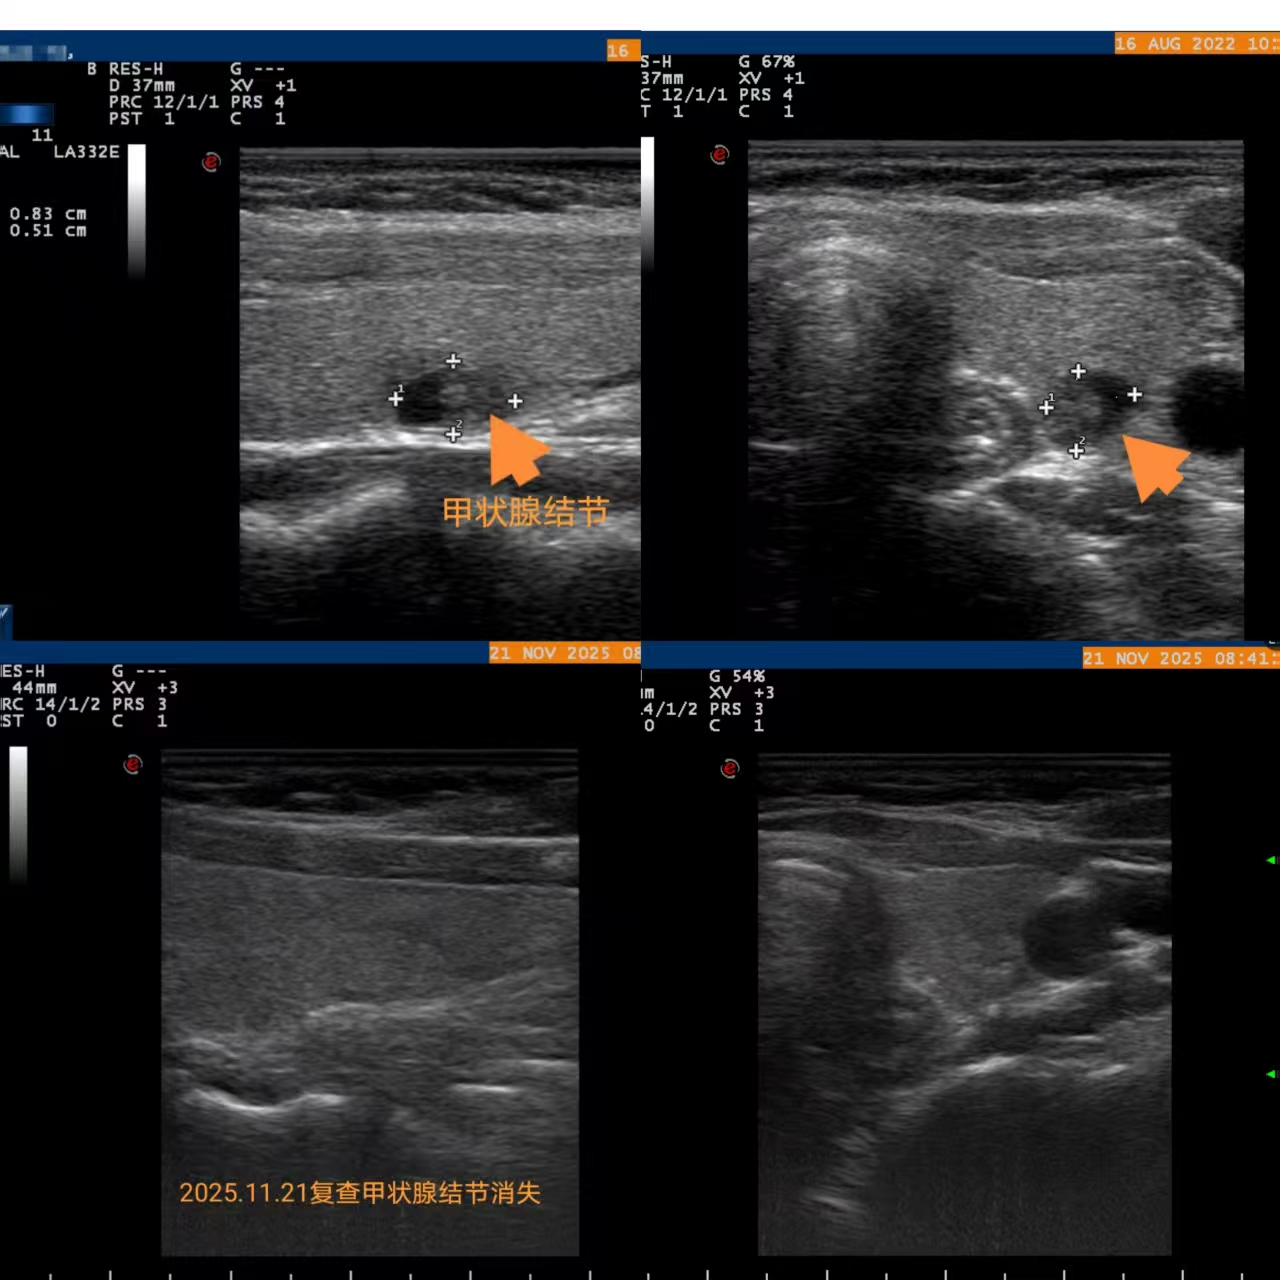

术前检查提示,袁女士的甲状腺结节位于左叶中部,大小约8.3×6.2×5.5mm。治疗过程顺利,术后半年,她在当地医院复查时发现结节已完全吸收消失。

2025年11月21日,袁女士因子宫肌瘤再次来院治疗时,同期复查甲状腺超声,显示双侧甲状腺未见异常,恢复良好。(如下图)